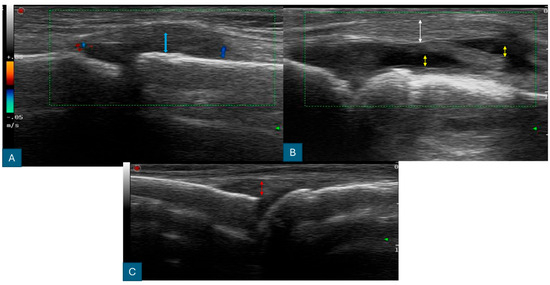

2.3. Ultrasonography Examination